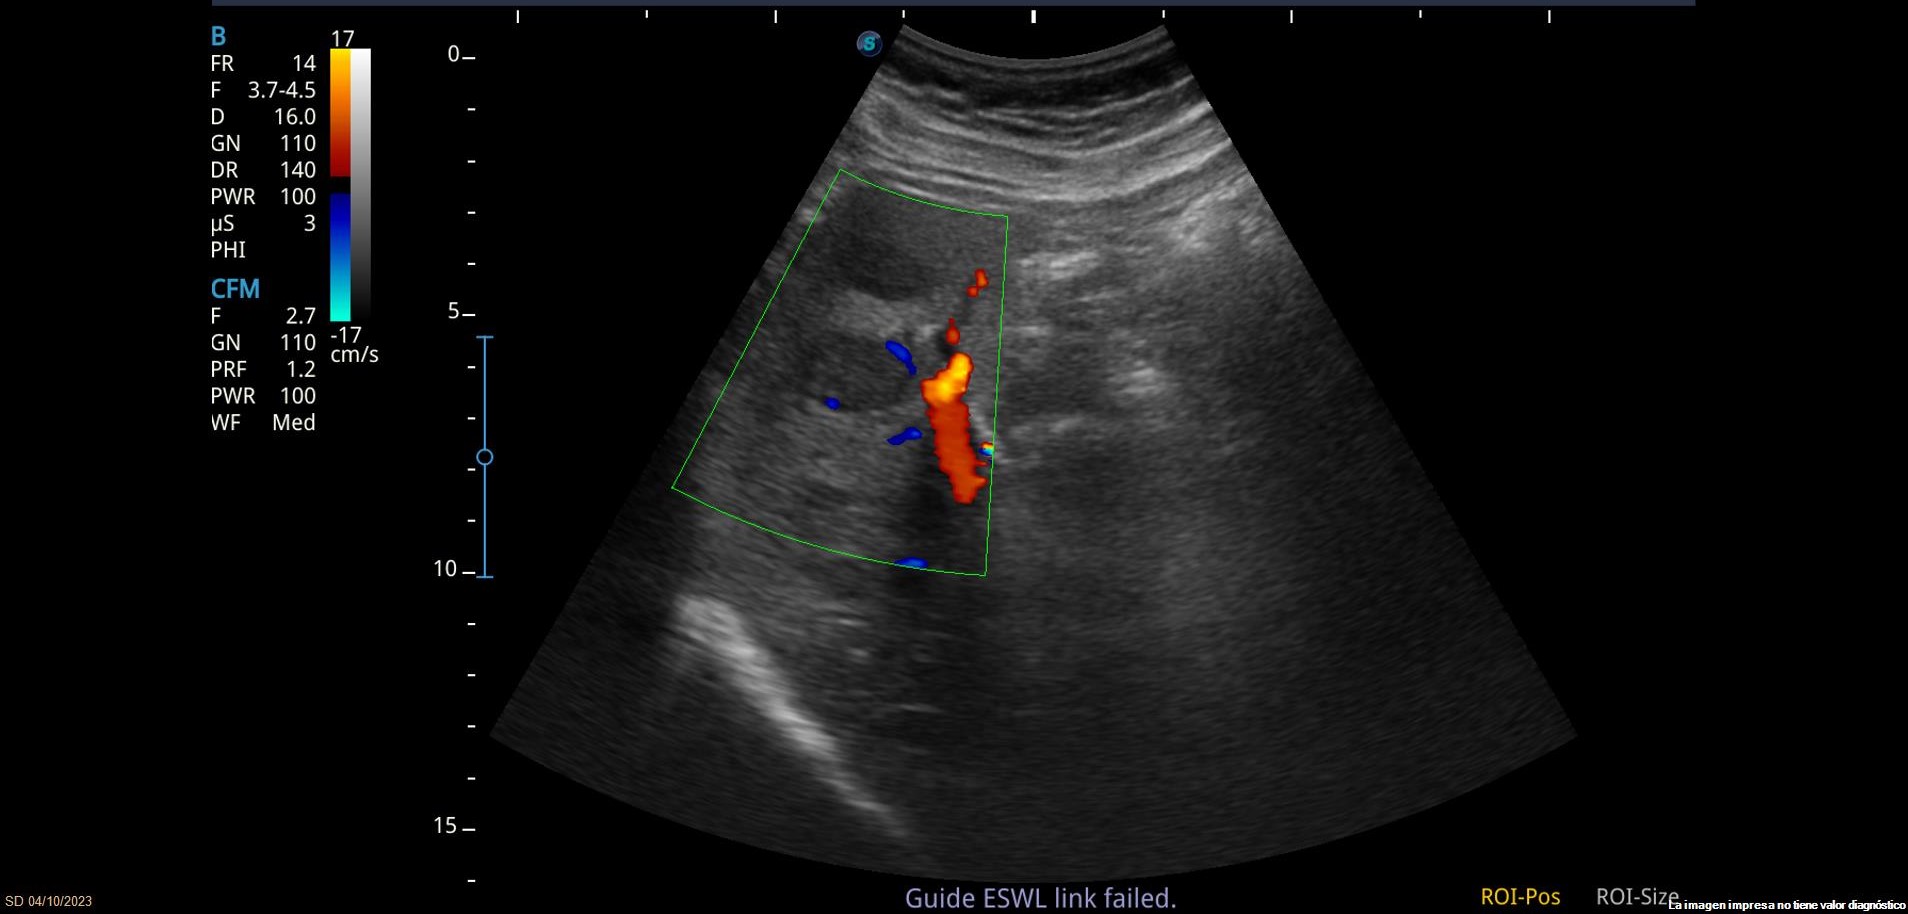

Se observan varias LOEs (lesiones ocupantes de espacio) hepáticas isoecoicas con parénquima hepático, la mayor de 3.5cm de diámetro, con leve vascularización. También se observa lesión hiperecoica con sombra posterior en parénquima hepático, sugerente de litiasis.